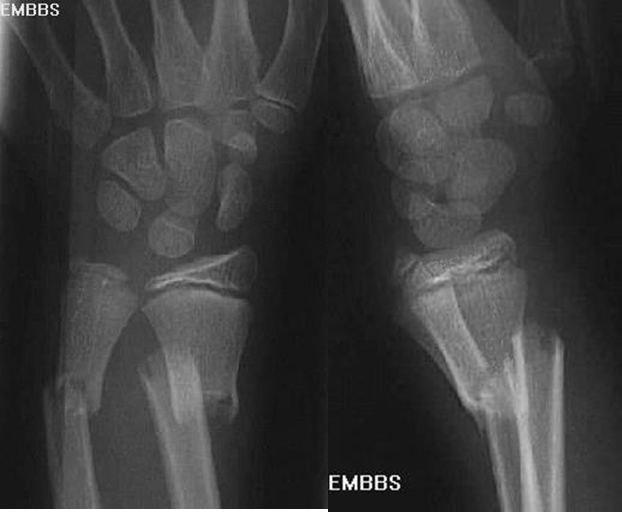

Colles骨折

桡骨远端骨折

骨折向掌侧成角

远折端向背侧移位

Smith骨折

正常腕关节

月骨周围脱位